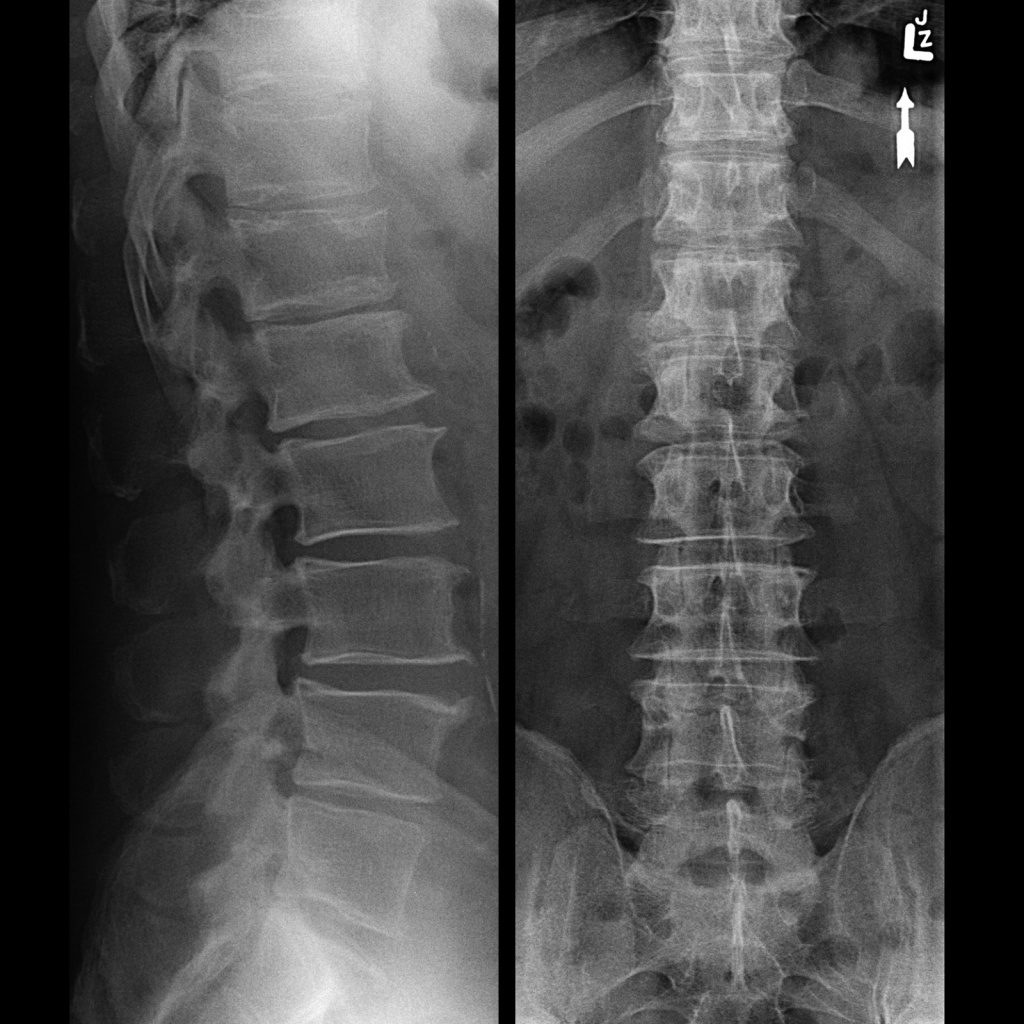

Применение рентгена в неврологии

Применение рентгена в неврологии можно условно разделить на две группы – исследование головного и спинного мозга, в частности рентген позвоночника. Являющихся мягкими тканями, проницаемыми для электромагнитного излучения, и костных тканей – костей черепа и позвоночного столба.

Рентген активно применяется в неврологии наряду с несколько более сложными методами – магнитно-резонансной томографией и компьютерной томографией и служит целям оценки состояния черепа и позвоночника.

С помощью рентгеновского снимка возможно диагностировать и визуализировать следующие патологические состояния:

• наличие травматических повреждений

• врожденные аномалии развития костных тканей

• длительно сохраняющаяся боль в позвоночнике

• пороки развития костей

• опухоли, злокачественные и доброкачественные, кисты, абсцессы

• дегенеративно-дистрофические заболевания (остеохондроз, межпозвонковая грыжа, спондилез)

• повышение внутричерепного давления.